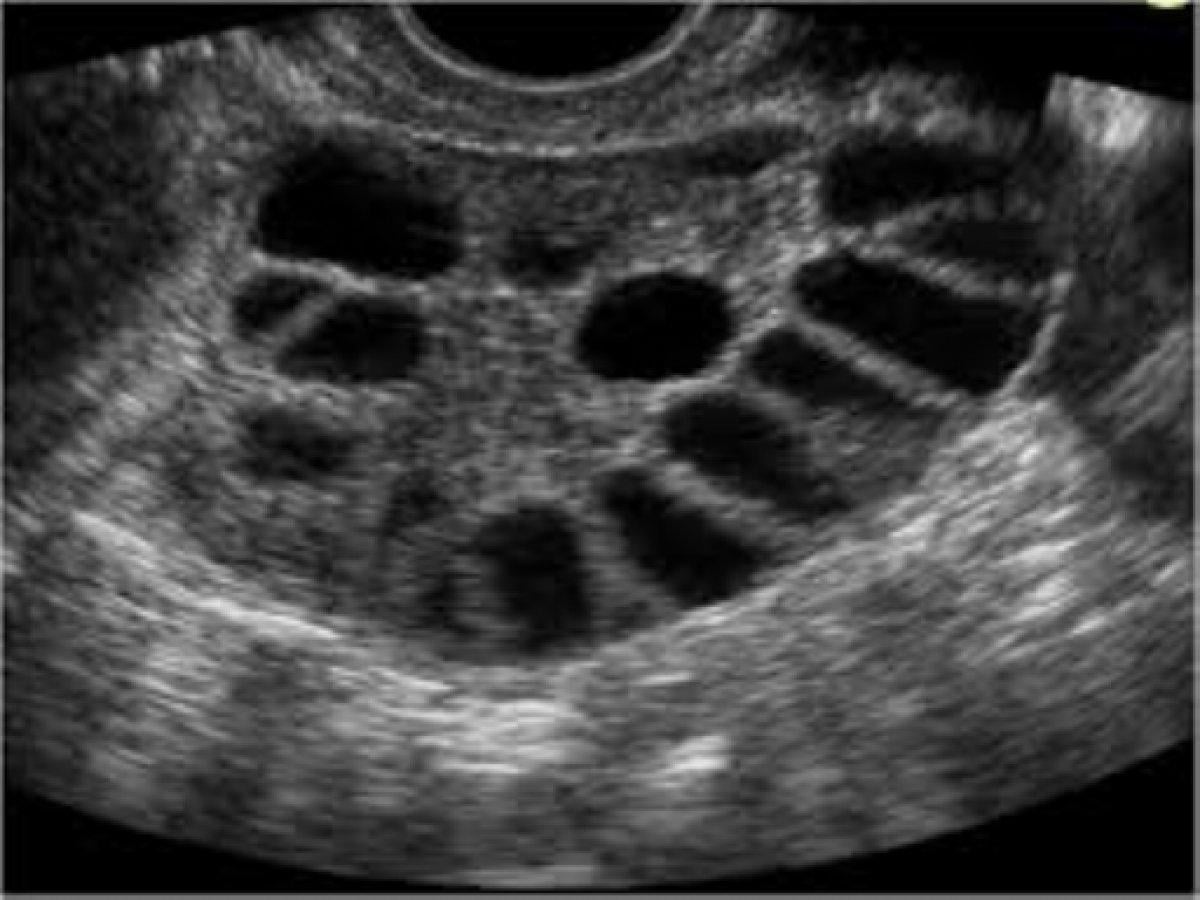

Tanı da ultrasonografi çok önemlidir. Yapılan vaginal ve pelvik ultrasonografi de yumurtalıklar ve rahimin detaylı incelenmesi gereklidir. Ultrasonografi de bir yada iki yumurtalığın multikistik (çoklu kist) görünümü tanı için önemlidir. Ancak her çoklu kistik görünüme PCOS denemez, laboratuvar ve klinik bulguların desteklemesi gerekir.